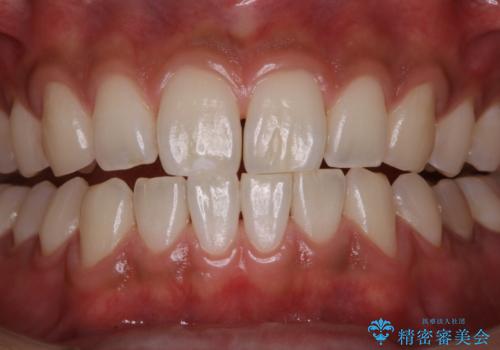

PMTCで清潔感のある明るい口元に

PMTCを行うことで、ご自身本来の歯の色になり自然な明るさになります。

口元が自然な明るさになることで、より清潔感のある印象になるため結婚式・行事やイベント前などにもPMTCを行うはおすすめです。